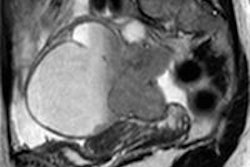

Whole-body PET/CT shows the difference between AW-OSEM (left) and AW-OSEM with PSF (right) and the increase in SUVmax by adding PSF. Image courtesy of Dr. Søren Holm.The reader graded the overall image quality of the whole-body AC-PET images on a five-point scale, with 1 as "very poor" and 5 as "very good." The physician also tallied the number of visible lesions from the AC-PET images based on anatomical regions, such as the head and neck, mediastinum, lungs, liver, spleen, abdomen, pelvis, bones, and other areas.